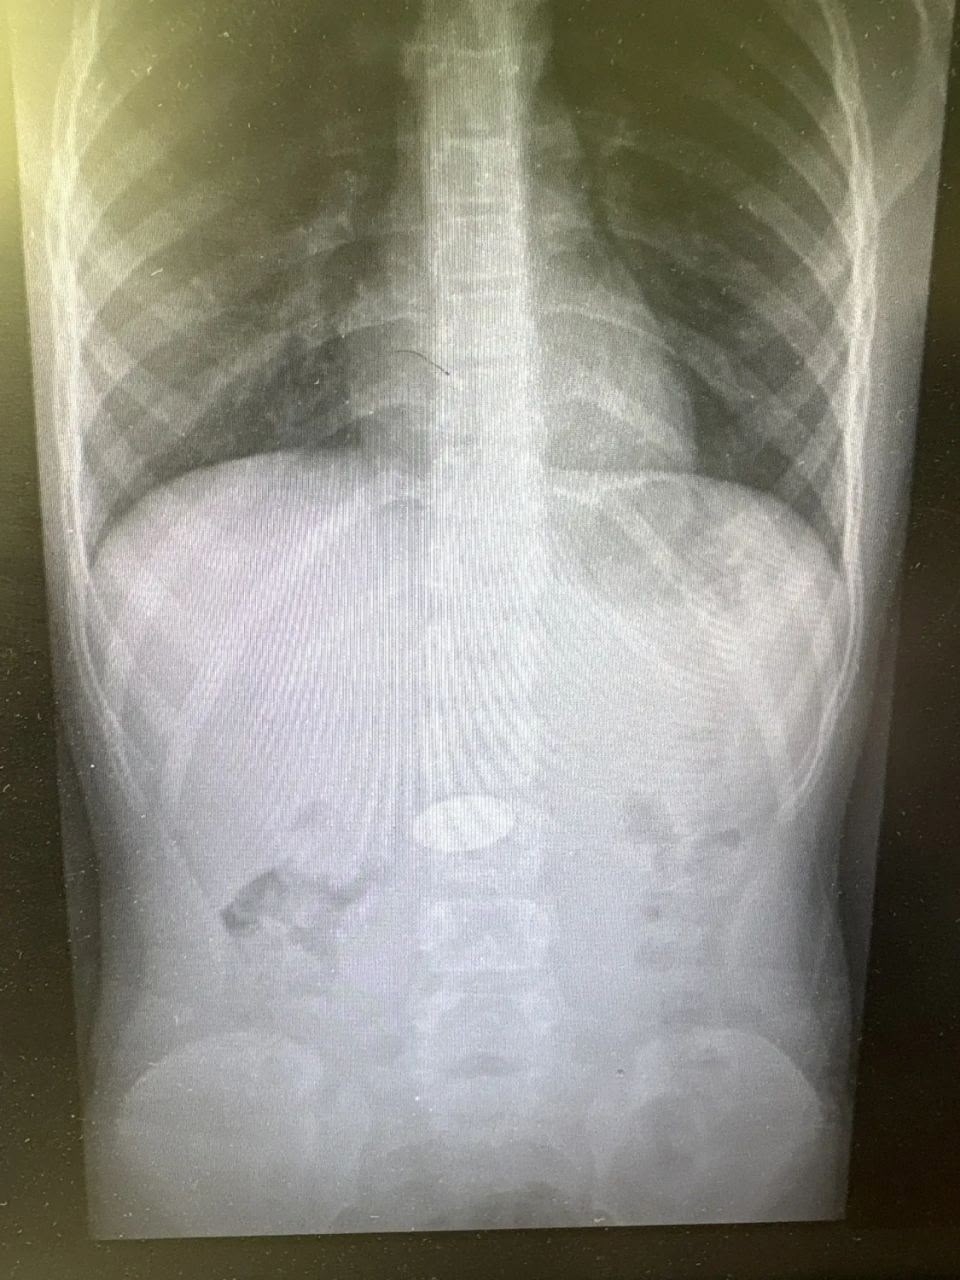

❤️ Чудо в Волгограде: врачи спасли малыша, который проглотил 5‑рублёвую монету!

Ребёнок поступил в больницу № 7 с инородным предметом в желудке. Благодаря профессионализму медиков монету быстро извлекли — и маленький пациент вернулся домой!

💬 "Наше отделение ежедневно принимает детей с инородными предметами. Особенно опасны батарейки и неодимовые магниты. Они не просто вызывают дискомфорт, а могут привести к тяжелой инвалидности или даже смерти. Родители часто недооценивают риск, а потом мы сражаемся за жизнь ребенка", — говорит детский хирург больницы №7.